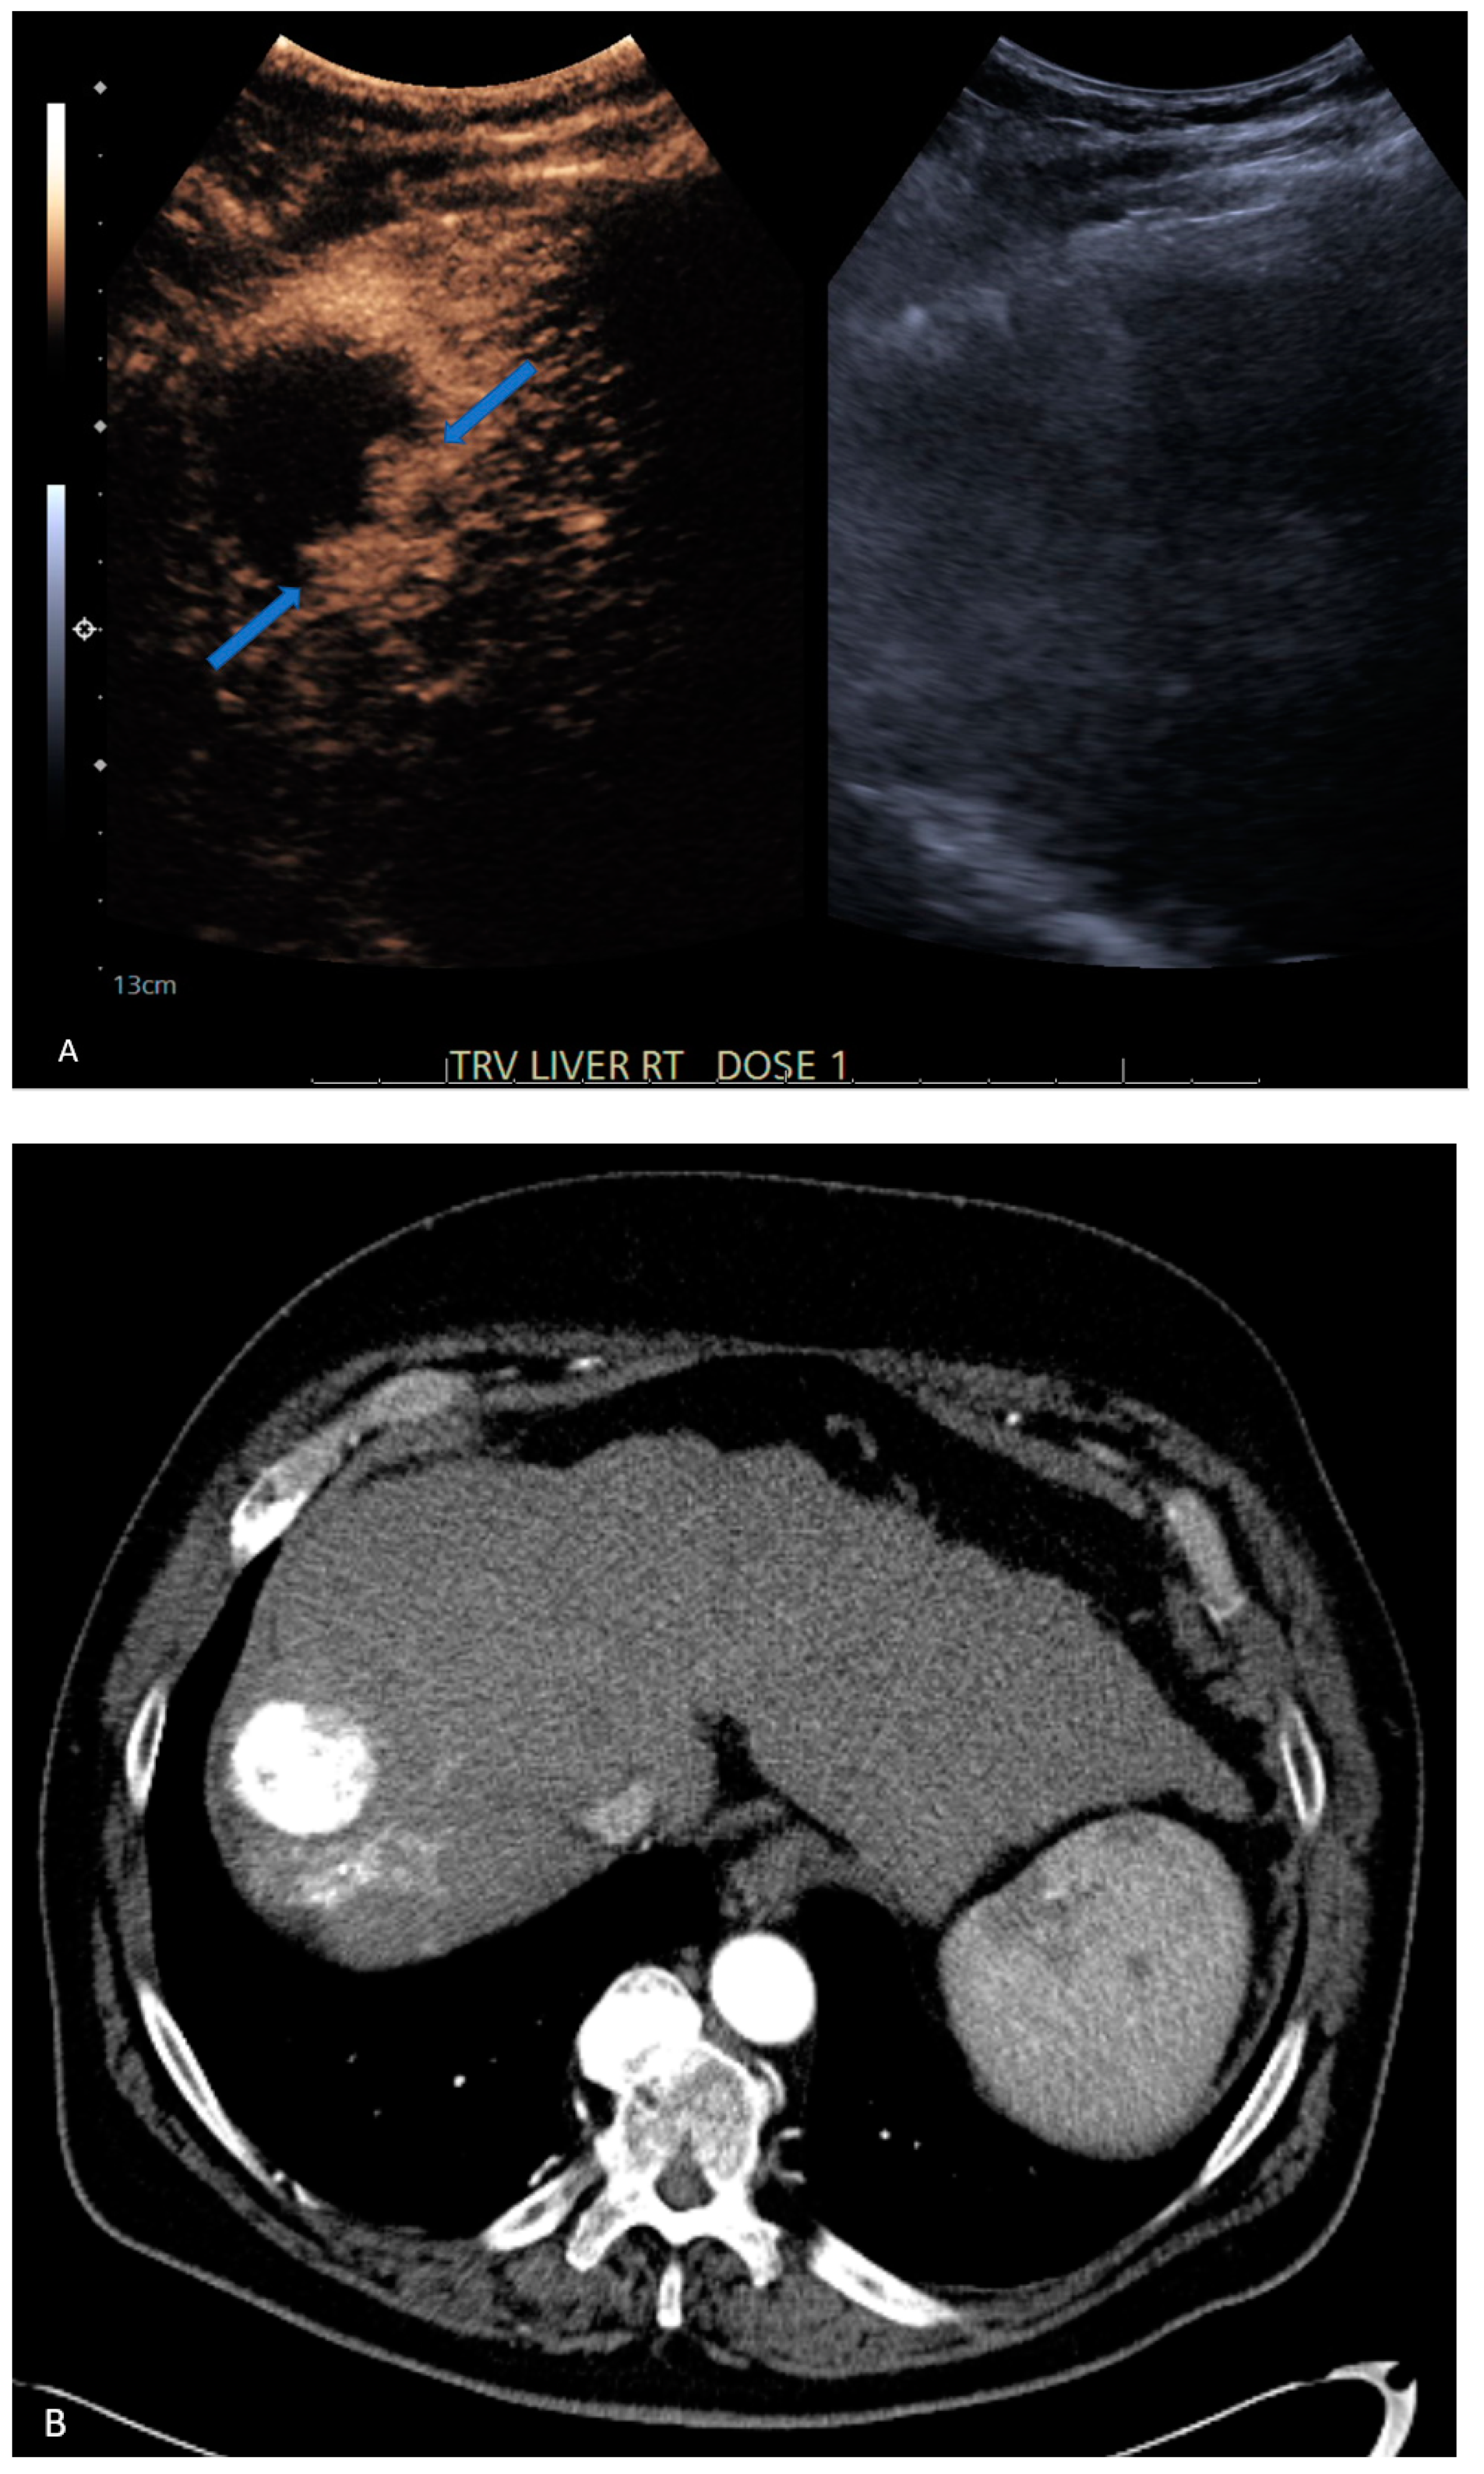

| 6 | CEUS | Target | LR-viable | CT missed subtle disease at the periphery of the treated HCC (Figure 2) |